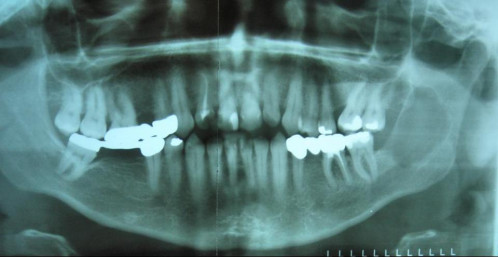

Schwellung an der inneren Wange stört beim Kauen

Fall-ID: 540

ICD: K09.0

45-jähriger Patient. Er habe seit ungefähr 3 Wochen eine leichte Schwellung der linken Wange bemerkt, auf die er ständig draufbeiße.

Welche Aussage zur gezeigten Bildgebung ist richtig?

- AEs ist eine scharf begrenzte Läsion zu erkennen.

- BEs liegt eine osteolytische Läsion vor.

- CDie Läsion könnte einer Zyste entsprechen.

- DDie Läsion könnte einem soliden Weichteiltumor entsprechen.

- EAlle Aussagen sind richtig.

Bildgebung - OPAN präoperativ